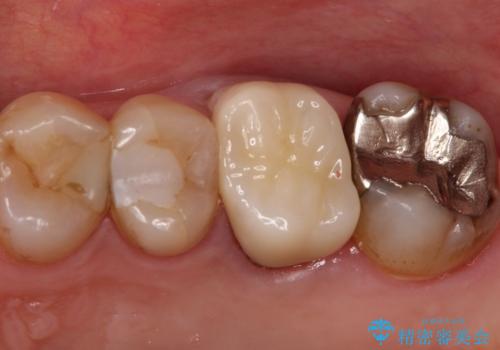

発見の難しい虫歯。根管治療から被せもの治療

- 定期検診にて被せものと歯との隙間に虫歯を発見した患者様です。

根管治療から被せもの治療(ベレッツァ)まで行いました。(根管治療は林院長に依頼)